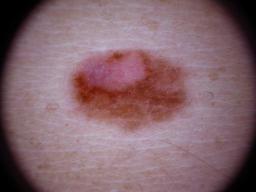

Melanoma and Nevus Dermoscopy Images with Confirmed Histopathological Diagnosis

Description:

Collection defined by Dr. Jorge A. Rios-Duarte for a research project.